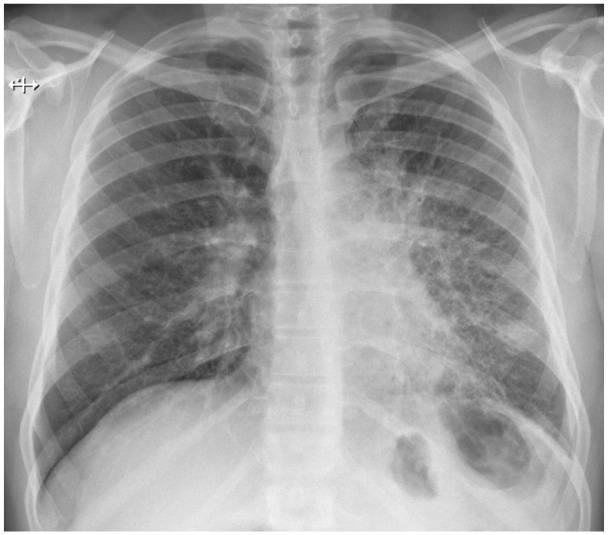

We present a case of a 42-year-old male with sarcoidosis manifesting as endobronchial mass-like lesions, a rare and atypical presentation of the disease. Sarcoidosis typically involves the respiratory system, but its occurrence as endobronchial polyps mimicking malignancy is uncommon. The diagnosis was confirmed through bronchoscopy and biopsy, revealing non-caseating granulomas. Treatment with corticosteroids led to significant clinical improvement. This case underscores the importance of considering sarcoidosis in the differential diagnosis of endobronchial masses and the role of biopsy in confirming the diagnosis.